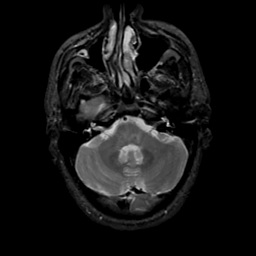

MR Study #20 October 6, 1991 -- Slice #11

[Home][Help][Clinical][Tour 1][Tour 2] Slice 11